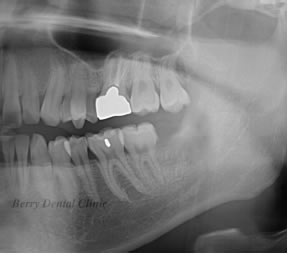

親知らずの抜歯 治療例

親知らずの抜歯も消炎処置をしても治癒しない場合は処置を行います。

左の実際のお口の中の画像ように親知らずが横になっている為プラークがたまりやすく親知らずの前の歯も虫歯になっています。

舌の2枚の画像はそのレントゲン画像で、左側はピンク色の歯ぐきを入れて加工しています。

右の画像のように歯ぐき画像のピンク色の部分を除去すると矢印の部分の親知らずの前の歯に黒い画像があり、それが虫歯になっている事を示します。

そのまま放置しているかぎり虫歯の歯の治療ができなので、抜歯になります。